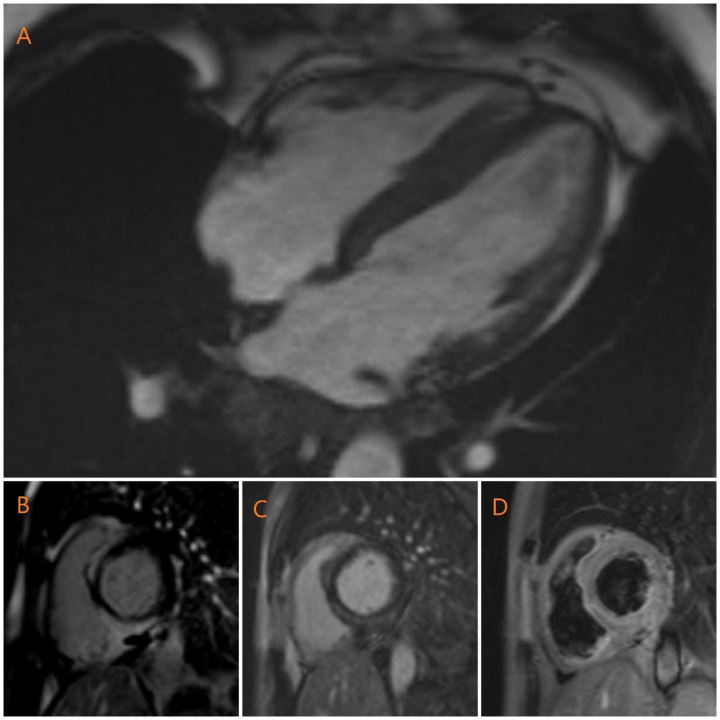

Sarcoidosis is a challenging disease characterized by the formation of granulomas in multiple organs. It presents with a variety of clinical symptoms, making diagnosis difficult for physicians. Myocardial involvement in sarcoidosis is rare, but it worsens prognosis and can lead to mortality. Physicians face challenges in diagnosing cardiac sarcoidosis due to its wide range of symptoms. Cardiac sarcoidosis that affects only the heart without involvement of other organs is extremely uncommon. In this case, we examine the scenario of a middle-aged man who experienced palpitations and was diagnosed with ventricular tachycardia. He remained in stable condition without any other clinical signs suggestive of sarcoidosis. This case highlights the importance of considering sarcoidosis as a potential diagnosis in patients presenting with palpitations and ventricular tachycardia on electrocardiogram, particularly when these symptoms are accompanied by sudden new-onset systolic dysfunction despite normal coronary arteries.